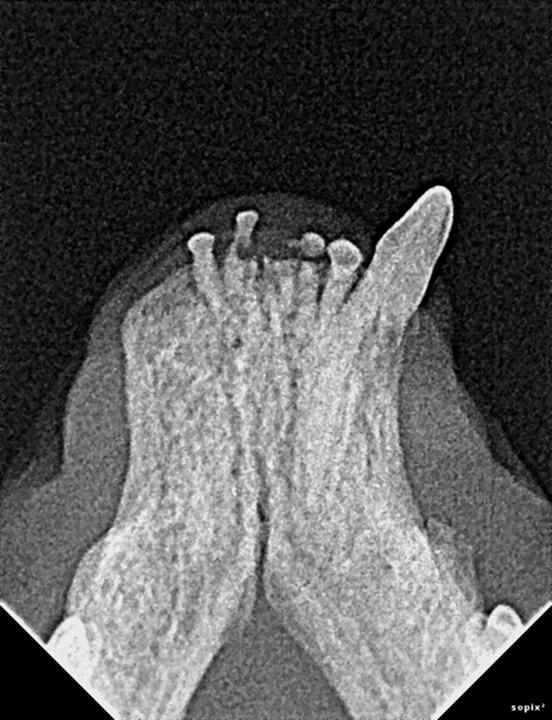

Differential diagnoses for the missing teeth include trauma, impaction, teeth were never present, tooth resorption, and periodontal disease. (See Figure 1.)

FIGURE 1

The patient is missing teeth, but has no history of previous extractions.